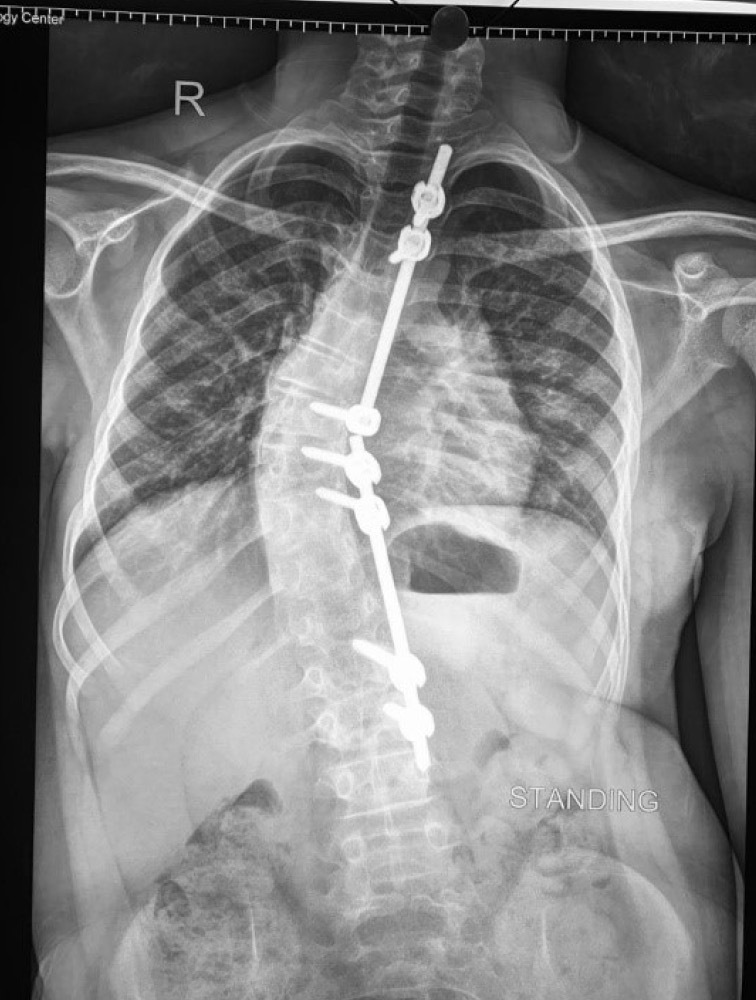

Background: Distraction-founded techniques such as traditionally growing rods or magnetically controlled growing rods are the almost globally accepted management patterns for early onset scoliosis. However, periodic lengthening operations are still needed. Moreover, an MCGR is difficult to contour, and implant-associated problems are common. We developed concave side apical control of the growing rod in which an additional anchor site is inserted at the apex to enhance stability and assist in the adjustment of axial deformity.

Results: In this study, 15 patients were involved. The mean age was 7 years. The mean preoperative Cobb angle was 48°, which postoperatively became 12° with the percentage of coronal correction reaching 75.73%. The mean Cobb angle degrees of correction were 39°. T1-S1 height increased by 10 mm/year. Postoperative complications occurred in two cases with single rod technique and rod breakage.

Conclusions: The concave side apical control of the growing rod seems to be a hopeful surgical procedure for the management of EOS. Curve correctability in patients was 60% and can be sustained for a minimum of 2 years. Reoperations and complications might not be constricted, but the complication frequency looks more reasonable than in the current systems.